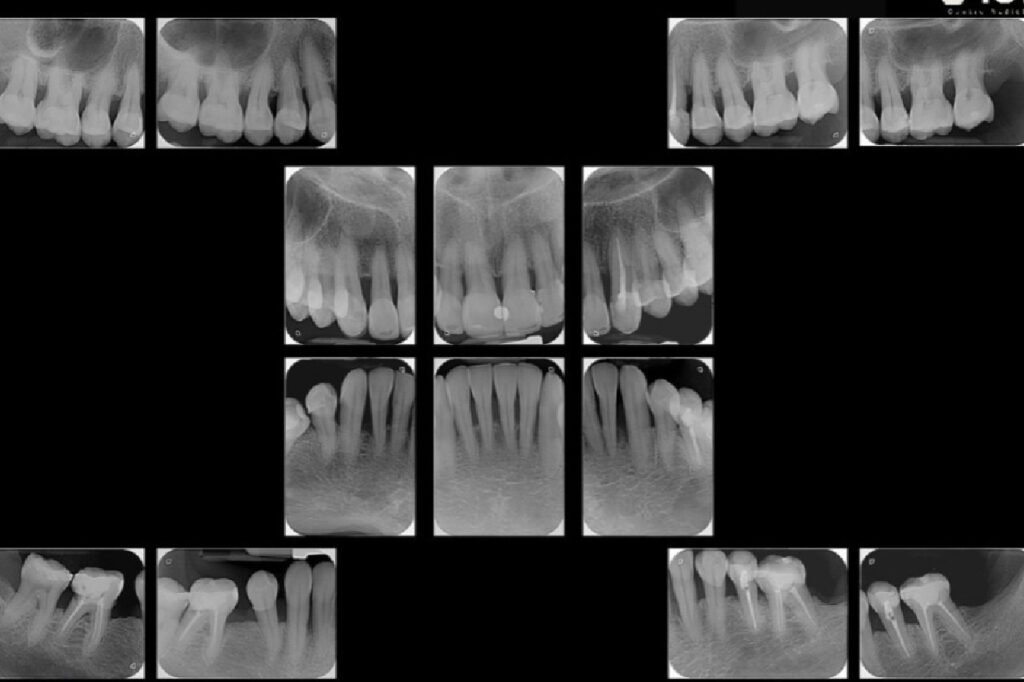

Radiografías Intraorales

- Juego periapical completo

- Periapical parcial

- Periapical parcial milimetrada

- Juego periapical milimetrada

- Coronal Parcial

- Coronal Completo